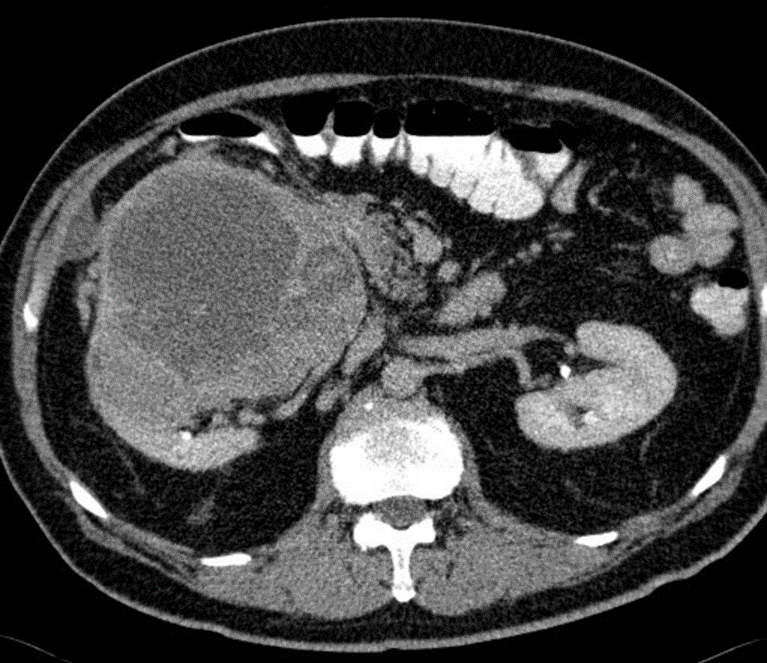

Axial CT of the abdomen after oral and IV contrast medium administration

A large, relatively sharply demarcated tumor can be seen in the right kidney. The CT shows a central, hypodense, necrotic area, which is surrounded by a solid, contrast enhanced, capsular region . This finding is characteristic of renal cell carcinoma.